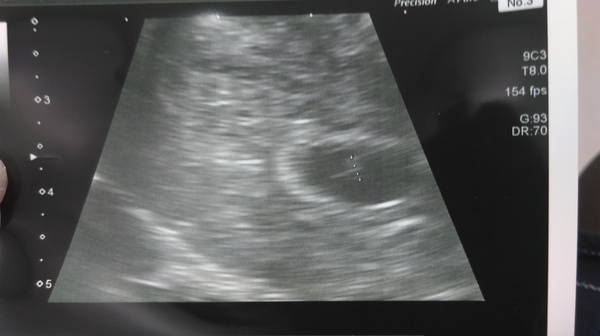

Scan is over

I saw my little bean Smile

She said she couldnt comment on viability because too soon but there is a pregnancy sack and it is in the tight place (no ectopic)

She booked another scan in 2 weeks time to see then. She couldnt see my ovaries to diagnose PCOS today because your ovaries change when pregnant.

I am relieved that the bean is in the right place. Time will only tell if it becomes a person or not

Thank you!! She only saw the pregnancy sack so not much but she said to the receptionist "this lady is pregnant and we need to book her another scan"